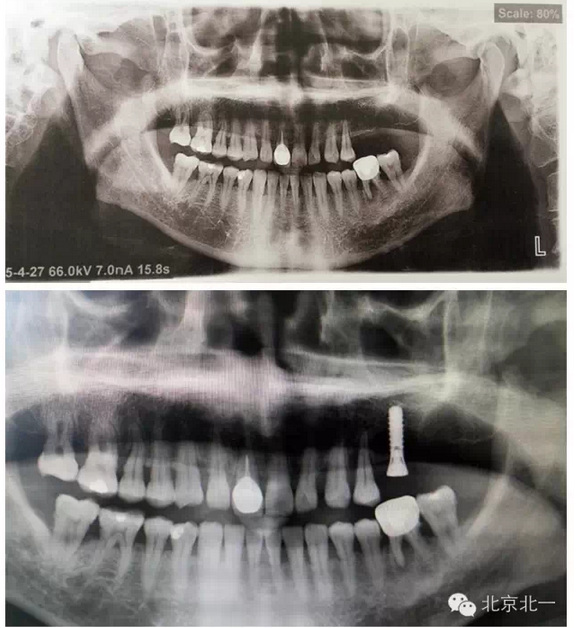

7 植體備份不合理, 無備骨粉骨膜, 術(shù)中情況特殊,需要植骨蓋膜。(圖七、手術(shù)沒有PLAN

B計(jì)劃,無骨粉骨膜,無大一號(hào)種植體,,有CBCT,拔牙后已經(jīng)2年,打開后拔牙窩沒有愈合,要植骨有木有,只能放棄一顆植入,等待下一次了)